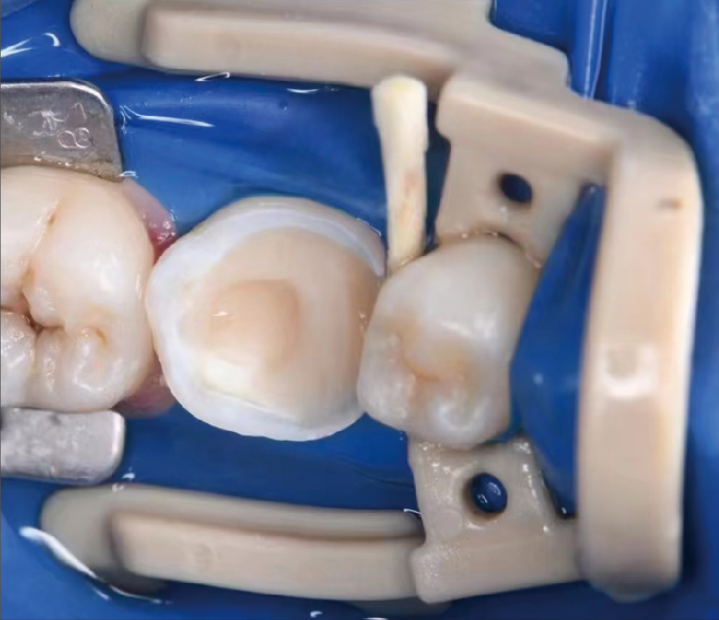

Para fijar el dique de muelas en casos de restauraciones de clase II con extensión distal.

Coloque la pinza en el premolar con unas pinzas para dique de muelas.

Al utilizar el dique de muelas en la extensión distal, la pinza fija el dique de muelas y ayuda a dejar suficiente área de tratamiento